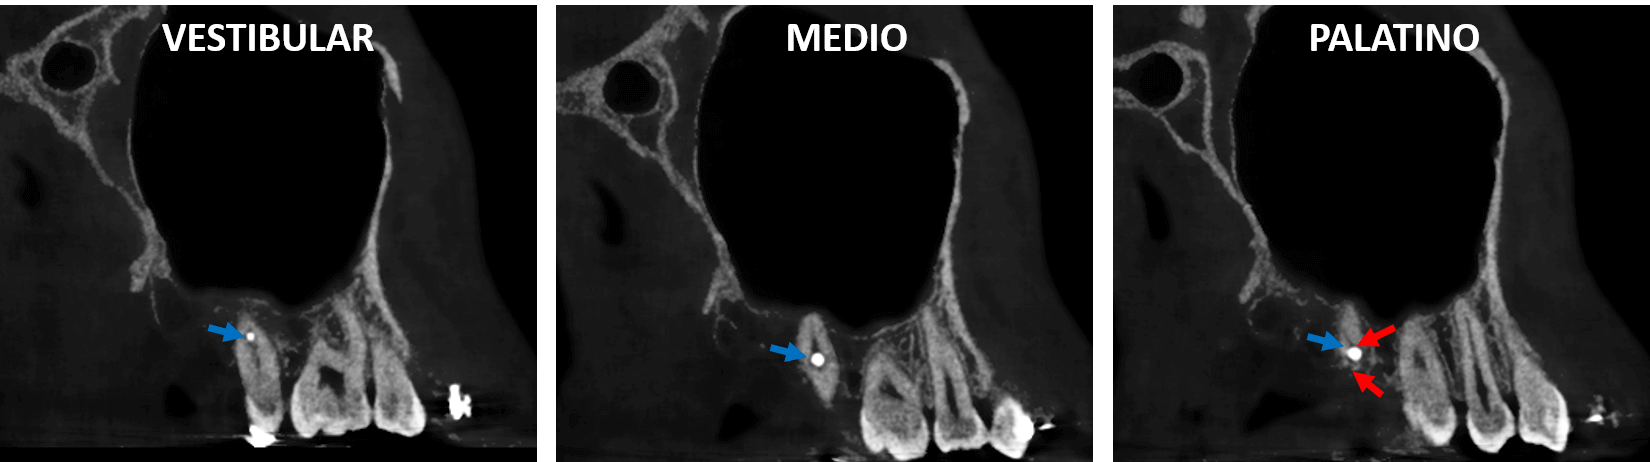

Fig.2

En la evaluación con tomografía volumétrica cone beam, en cortes transaxiales (Fig. 2) del órgano dentario 17 se observa una imagen hiperdensa (flecha azul) perforando la raíz palatina y condicionando la presencia de trazos de fractura (flechas rojas). La imagen hiperdensa se trata del dispositivo de fijación quirúrgica proyectado sobre el OD 17.